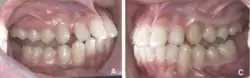

In Angle's classification system for malocclusion, a Class II bite (Figure 1) occurs when the lower jaw (mandible) is positioned more behind relative to the upper jaw (maxilla). This misalignment means that when the teeth come together, the lower teeth bite significantly behind the upper teeth[2] creating a large horizontal gap between upper and lower teeth. It is defined as increased overjet, which is measured from the labial surface of the tips of the upper incisors to the labial surface of the lower incisors horizontally.[3]

Figure 1: Image depicting Angle's Class II division 1 malocclusion[4]